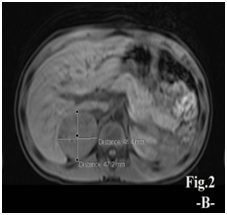

A 8.5- year-old boy presented with excessive pubic hair and other features of virilization for one year duration. On examination: he looks well, normal blood pressure, the height 121 cm (above 50th percentile), weight 30kg (75th percentile). Tanner stages for pubic hair, penile length (10cm) and testes volume (3 ml) were IV, IV, ІI respectively. No palpable abdominal mass, the rest of his physical examination unremarkable. Laboratory findings: FSH˂ 0.10 IU/L (1.4-15.4), LH 0.15 IU/L (1.2-7.8), testosterone 8 nmol/l (0.10- 1.04), 17 hydroxyprogesterone 2.1 ng/ml (0.2-3.5), cortical 346 mMol/L (168-728) ,Thyroid function tests, renal function tests and serum electrolytes were all normal. Imaging data: Bone age 11 years, abdominal ultrasonography showed well defined mass at right suprarenal region (49×48) mm., abdominal magnetic resonance demonstrated a mass at right suprarenal region measures (5×5)cm (Figure 1A) & (Figure 1B). Dynamic computed tomography of adrenal glands revealed: right adrenal mass (5×4x4)cm well defined associated with perilesional vessels, no invasion to surrounding structures. Brain magnetic resonance imaging was normal. Scrotal ultrasonography revealed both testes slightly enlarged in size with normal echogenesity chest X-ray normal. Based on the above data the interpretation was adrenal androgen-secreting tumor either adenoma or carcinoma. Therefore, the patient underwent right open adrenaloectomy: grossly; encapsulated mass, no invasion to surroundings, size (5×4x4). Histopathologic study was consistent with adrenocortical carcinoma confirmed by Immunohistochemistry (Figure 2 panel A) & (Figure 2 panel B). Postoperatively , on the first day, the patient complained of fatigue, and was found to have an undetectable morning serum cortisol level of ˂0.500 nmol/L (N: 171-536), Thus glucocorticoid replacement therapy was initiated, and he was scheduled for follow–up examination monthly for the first two years , scanning every 3 months for the first two years, 4 months for the next 2 years and every 6 months during the fifth year, since surgical treatment the patient has reported decreasing in features of virilization

Figure 1 Magnetic resonance images, revealing well-defined mass at right suprarenal region, measures about (5×5)cm.